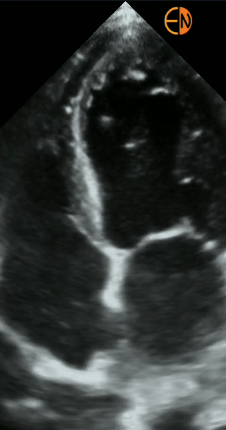

POCUS Cardíaco básico: Principais janelas cardíacas, avaliação da função sistólica dos ventrículos, avaliação do choque circulatório.

POCUS Cardíaco - medidas: Avaliação quantitativa do débito cardíaco, volume sistólico e função sistólica dos ventrículos.